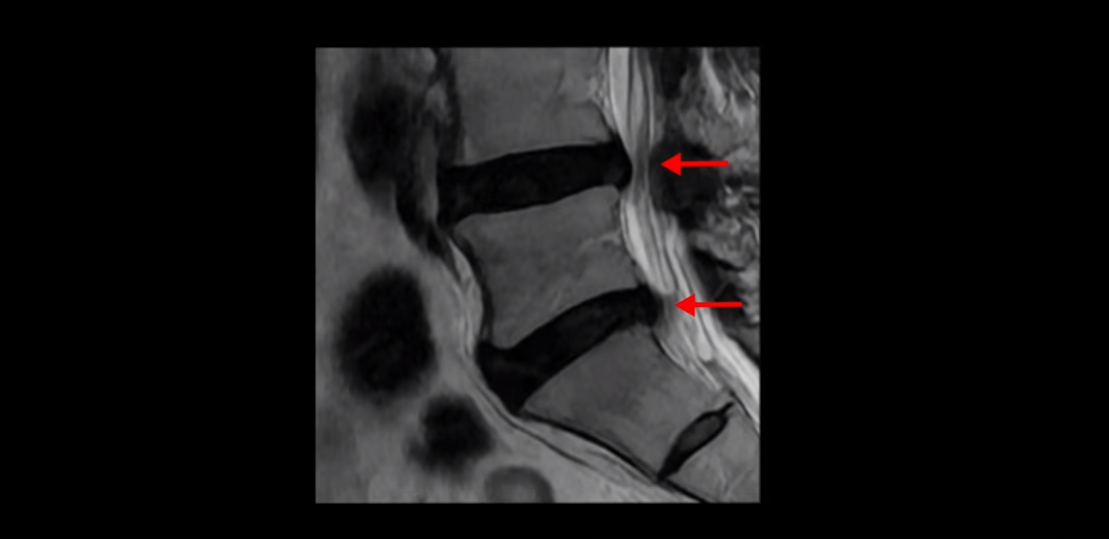

MRI를 보면서 설명해 드리겠습니다. 2마디에 퇴행성디스크가 있는데 심하지는 않습니다.

4번 5번에 척추관 협착이 있는데 신경을 심하게 누를 정도로 심하지는 않습니다.

오른쪽 왼쪽 신경 가지가 나가는 추간공도 좁아져는 있지만 아주 심하지는 않습니다.

이 환자분의 가장 큰 문제는 허리를 펴는 근육인 척추기립근이 상당 부분 지방으로 변해서 하얗게 보이고 기립근의 크기도 많이 작아져 있습니다.

이 기립근은 허리를 펴주는 근육인데 이렇게 문제가 생기면 허리가 구부러집니다. 또한 이분의 근육 상태를 알 수 있는 근감소증 검사에서 중증 근감소증 진단이 나왔습니다.

평균적인 동년배들에 비해 근육량이 많이 줄어든 겁니다. 이렇게 근육량도 많이 줄어들고 또 남아있는 근육이 지방으로 변한 상태에서 그나마 남아있는 근육들마저도 뭉치고 굳어서 제 기능을 못 하면 허리가 구부러지고 걸을 때 다리가 힘들고 아플 수밖에 없습니다. 그런데 근육 치료와 이런 근육의 문제를 MRI를 찍어보고 협착이 조금이라도 보이면 협착증으로 진단하고 주사 놓고 안 되면 수술까지 하는 경우들이 있습니다.